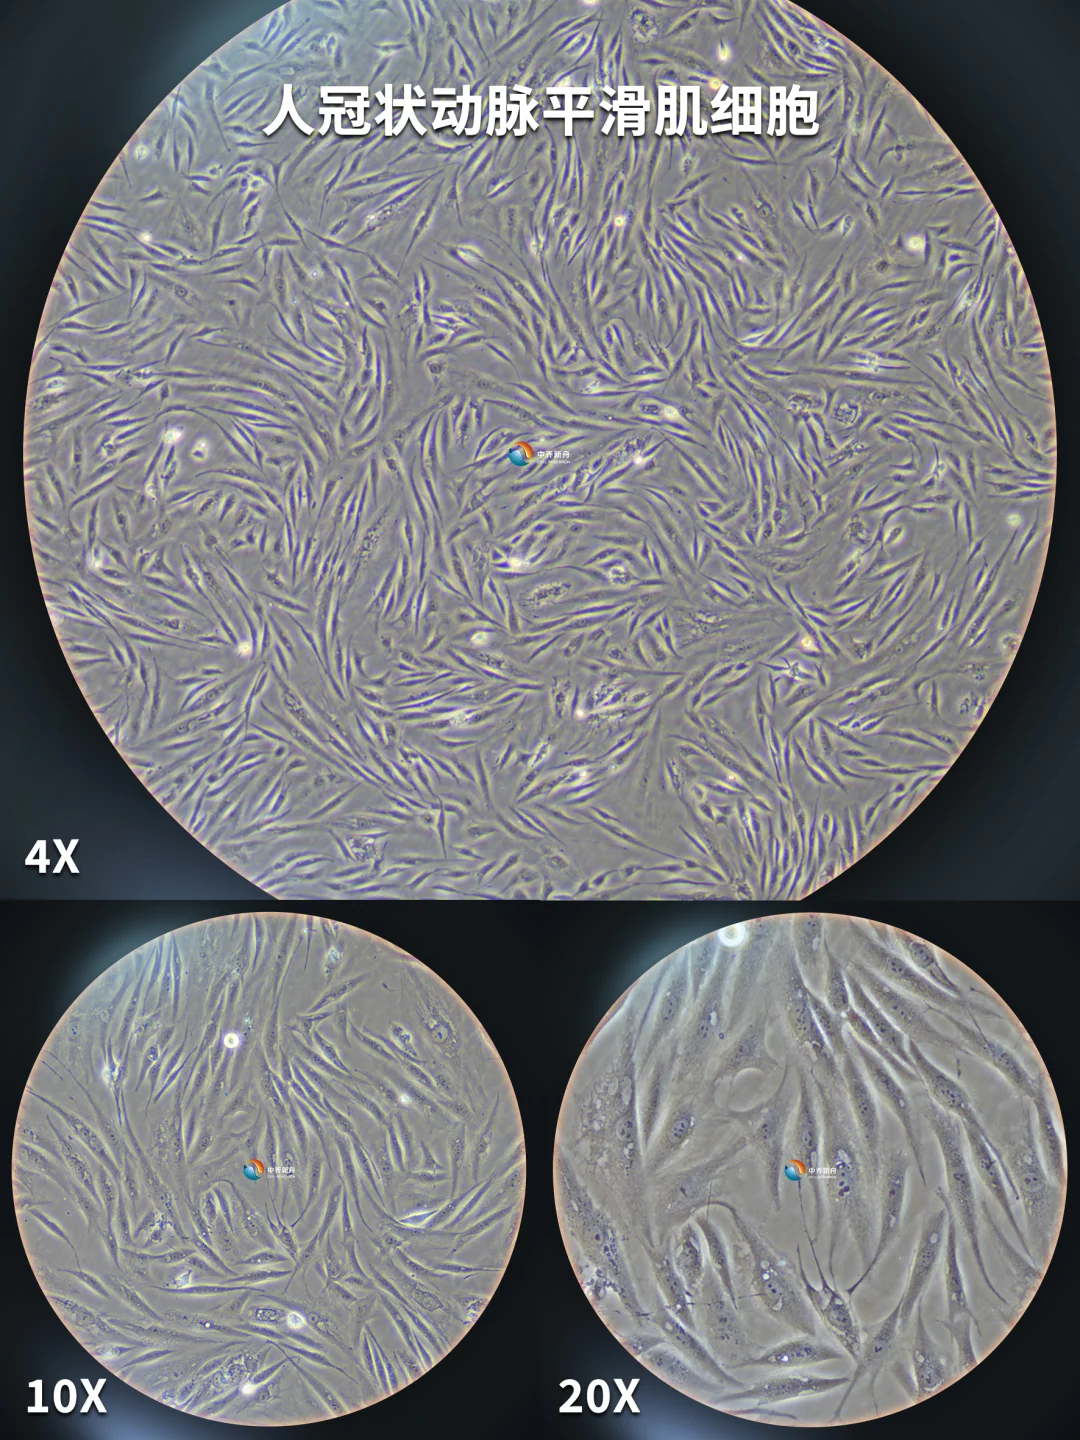

人冠状动脉平滑肌细胞,今天养这个细胞~